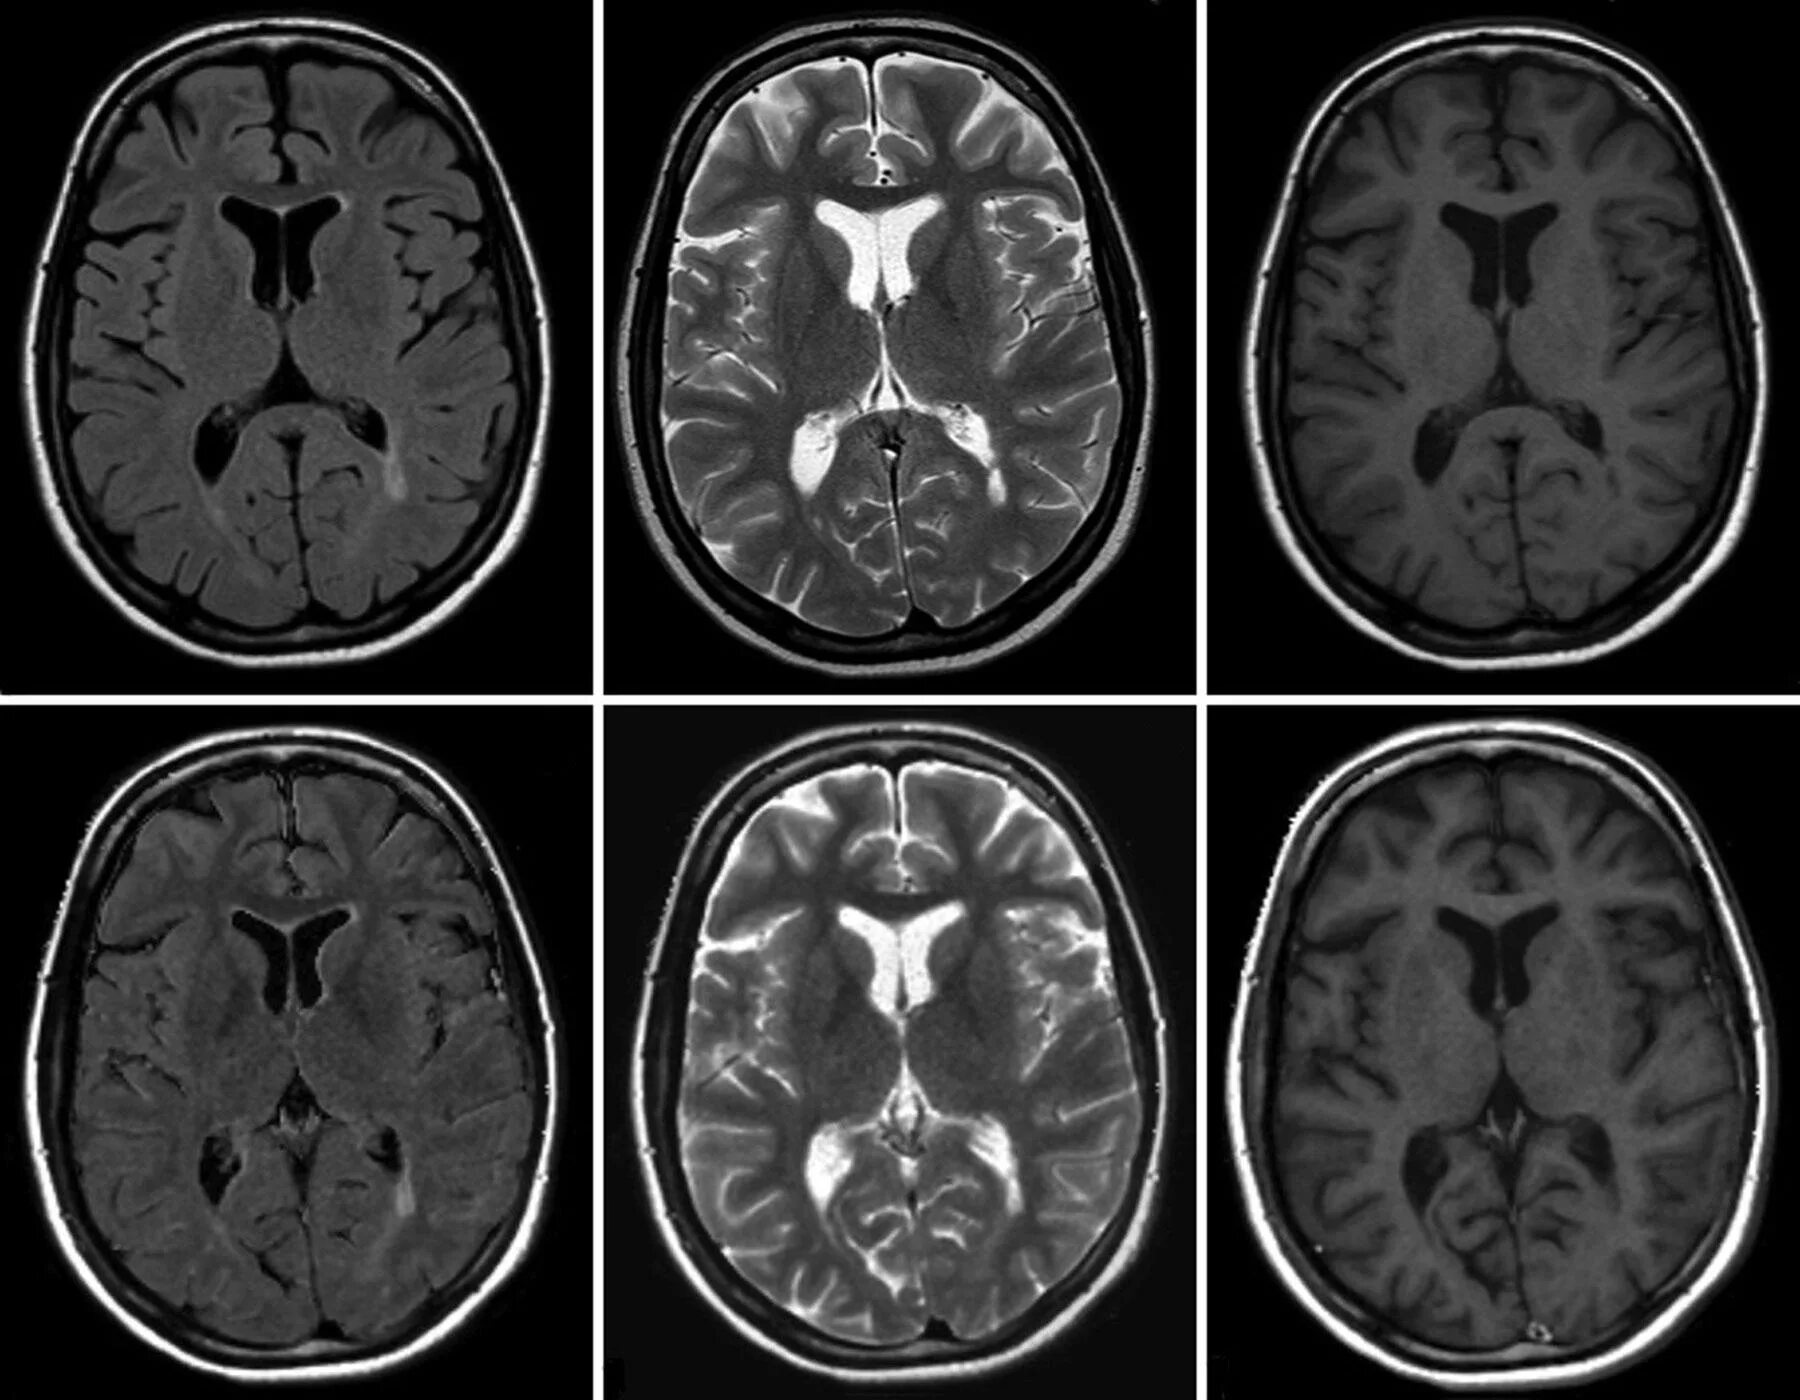

Что покажет мрт головного мозга с контрастом